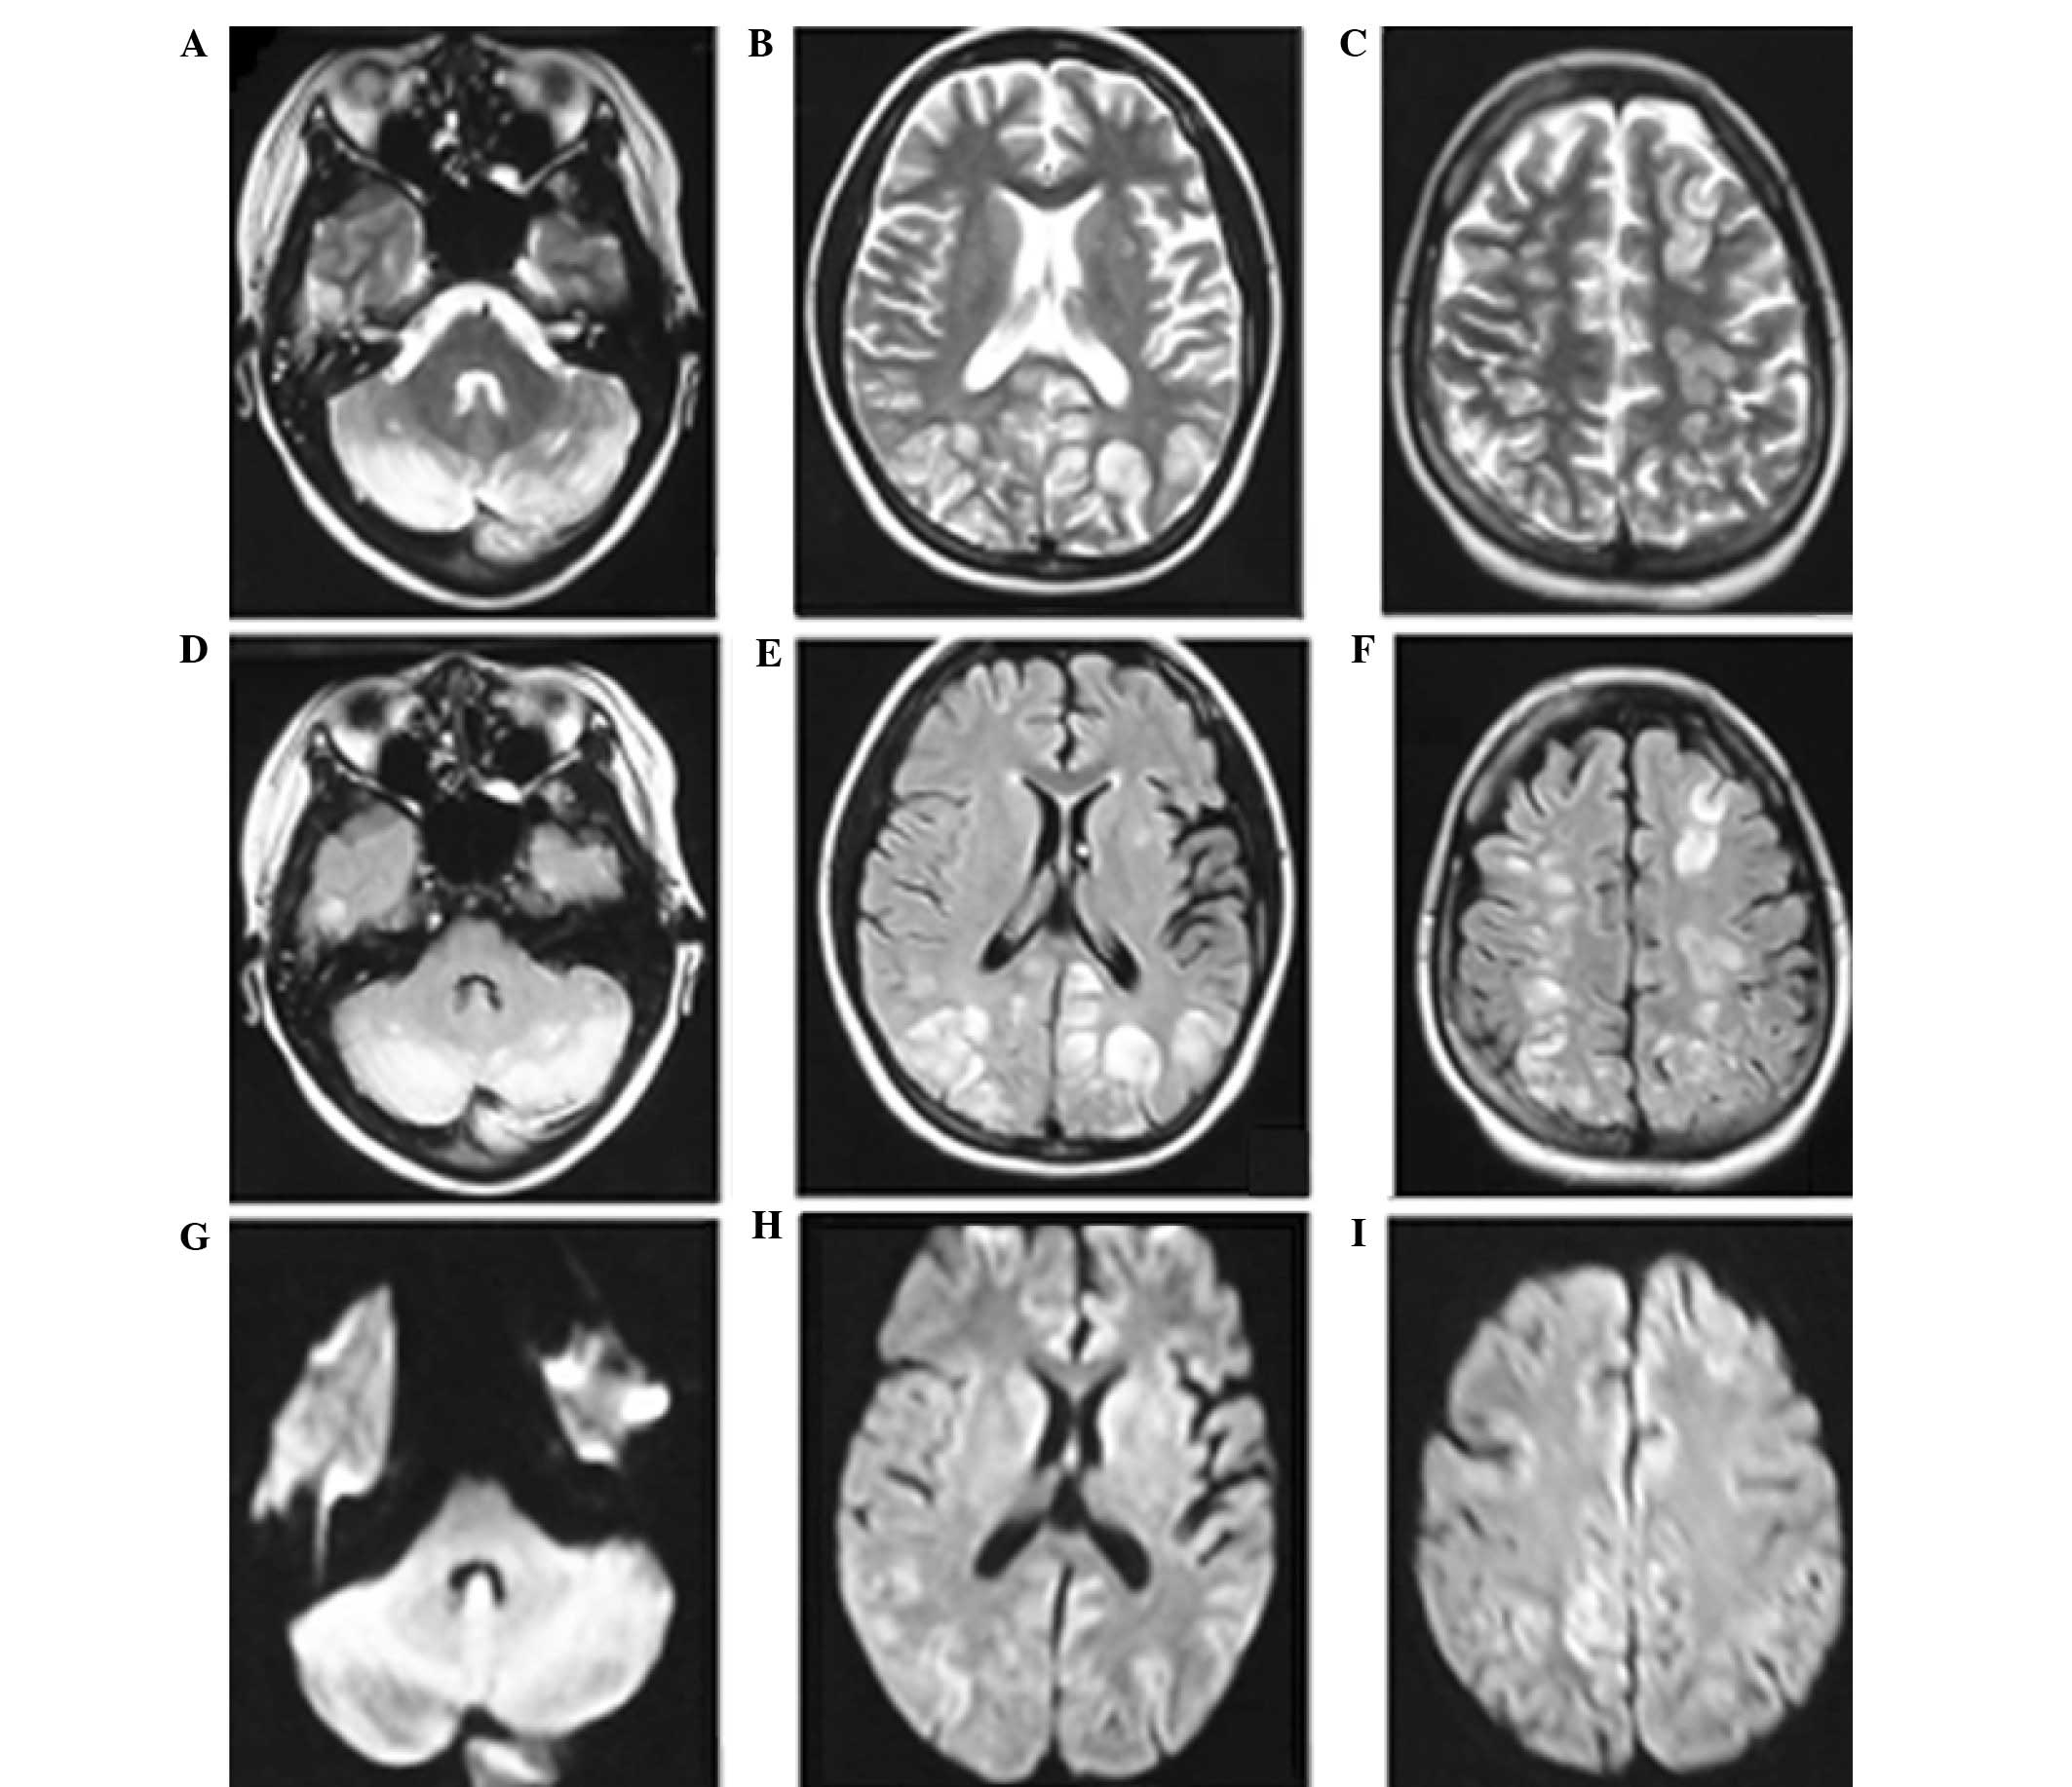

On day 4 after hospital admission, the patient received further head MRI and magnetic resonance arteriography/magnetic resonance venography (MRA/MRV) scans. The hyperintensity zones on T2-weighted images of the subcortex and white matter in the cerebellum, and occipital, frontal and parietal lobes were markedly decreased. The MRA scan revealed cerebral vascular focal vasodilation and vasoconstriction features with a string-of-beads appearance (Fig. 2), predominantly in the vessels of the posterior circulation of the brain. In addition, there was no intracranial sinus thrombosis; however, the MRV indicated venous sinus dilation (Fig. 2). Based on the results of tests, the diagnosis of reversible posterior encephalopathy induced by LPE was suspected. The patient was administered cefoperazone (4 mg per day), nimodipine (10–20 mg per day) and mannitol (250–500 ml per day). The temperature and blood pressure were normalized following treatment, and the patient experienced no further seizures during the remaining of the hospital stay. On day 11 after admission, the patient received further head MRI examination that indicated an almost complete resolution of the previous abnormalities (Fig. 3). Subsequently, the patient was discharged without any neurological sequela. The follow-up neurological examination after 1 month showed no abnormalities. During the two months follow-up examinations, no neurological symptoms were found.

LPE may manifest as RPES in which the most frequently affected areas are the subcortical white matter in the cerebral posterior circulation region (9). The less frequently affected areas include the frontal lobe, temporal lobe and basal ganglia. The characteristic radioimaging findings of RPES are reversible white matter hyperintensities on FLAIR combined with normal DWI scans, which indicate vasogenic edema (3,10). The edema reported in RPES cases is typically completely reversible. In certain cases, angiography may reveal a rosary bead-like appearance, representing diffuse cerebral vasodilation and vasoconstriction (3). The patient reported in the present study presented diffuse symmetric vasogenic edema in multiple regions, particularly the watershed zones of the parietal, occipital and frontal lobes. In addition, MRA suggested features of vasoconstriction or string-of-beads appearance, which are reflective of brain hypoperfusion (3,10). Notably, cerebral venous vasodilation was also observed in the current patient, which has seldom been reported in the literature (6,8). This abnormal venous vasodilation in addition to the arterial vasoconstriction were completely reversed following the aforementioned treatments, resulting in the patient's recovery.